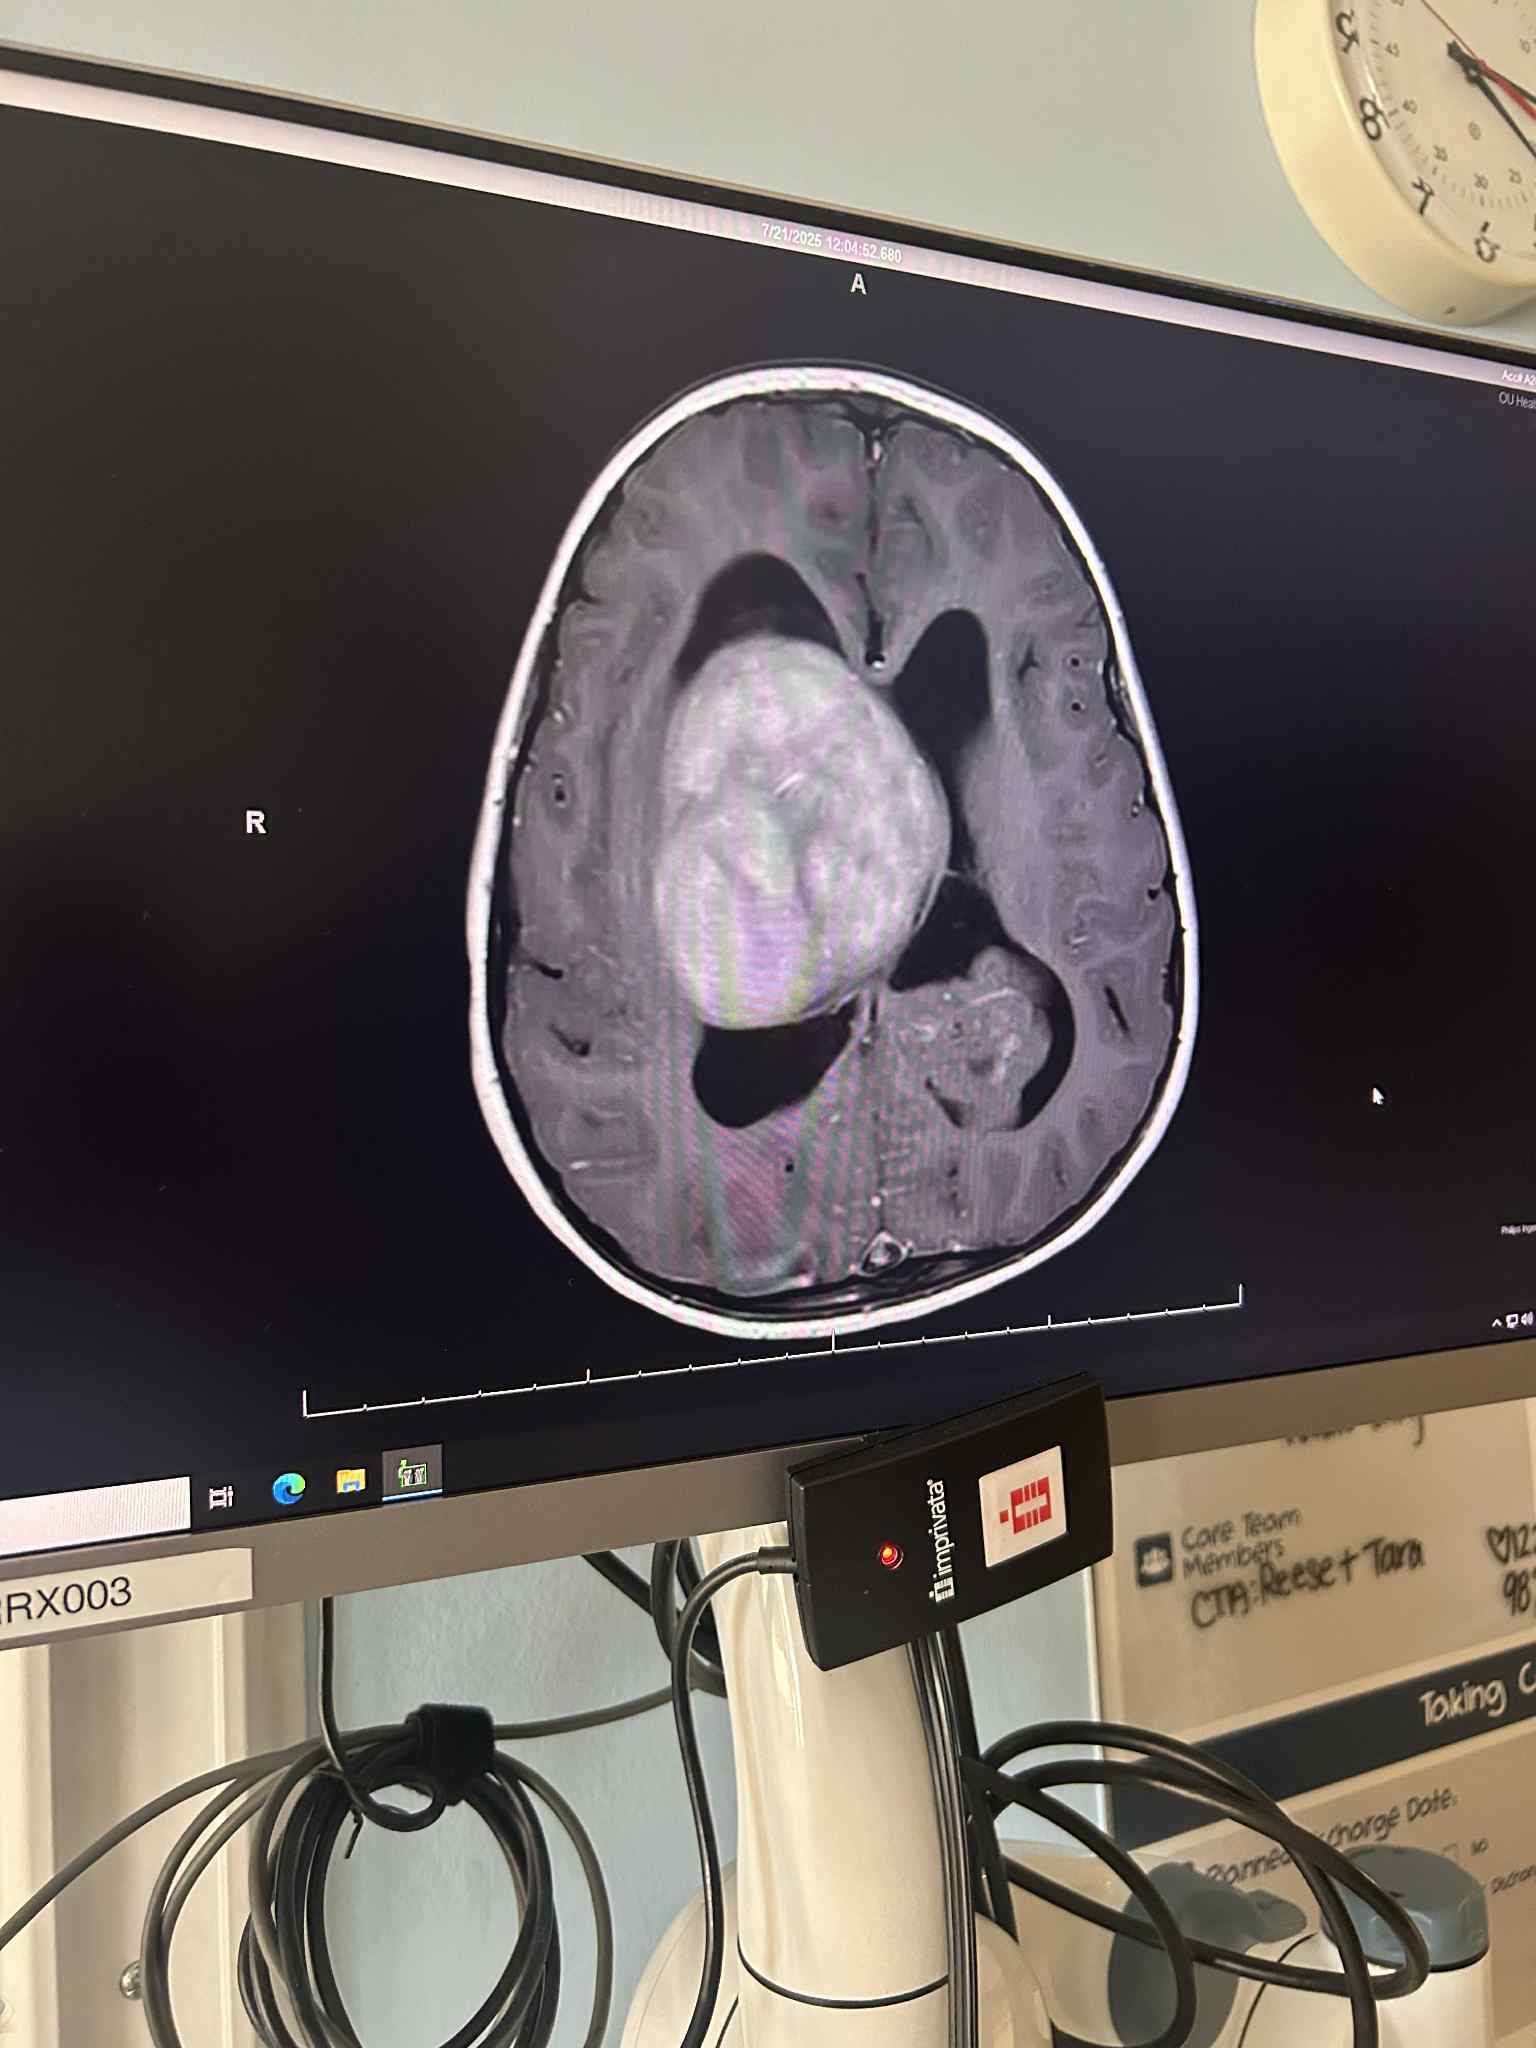

I am Julian’s mother. We are reaching out on behalf of our sweet, brave Julian Arvelo, who is only seven years old. Julian began experiencing weakness on the left side of his body, and it was noticed during an occupational therapy evaluation. Concerned, we took him to a neurologist, who ordered an MRI for him. Heartbreakingly, the MRI revealed a brain tumor measuring about 2 inches.

Julian has since been admitted to OU Children’s Hospital, where he is undergoing further testing and evaluation. On July 25, 2025, doctors will perform a right craniotomy, tumor removal, EVD, septum fenestration, & biopsy to learn more about the type of tumor and the best path forward for treatment.

Dr. Balsara is his neurosurgeon here at OU Children’s and I am so grateful for the amount of time he spent during this surgery to make sure he did the best job possible, safely. He removed most of the tumor if not all of it. he said there might be some right on top of the thalamus that he did not feel comfortable touching. He did say since it is a slow growing tumor and he believes because of that it is low grade. It is however a glioma, but results are still pending whether benign or malignant. They were also able to biopsy the other mass on the left side of his brain. We are still waiting results since it was so late last night.